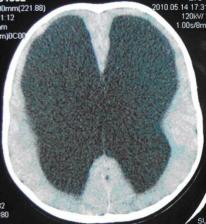

没错,儿童脑积水如果得不到及时的治疗就是如此。整个脑袋就像一个水桶,里面全是水,而真正的脑组织只有,这么一点(图中白色,而黑色的部分全是水):